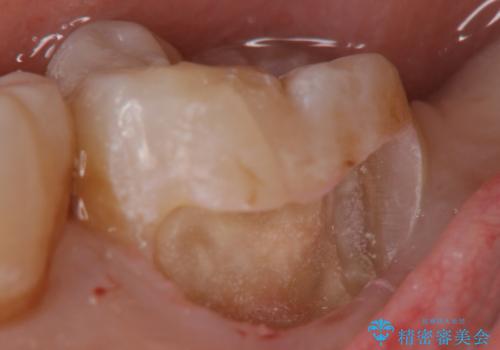

- 出産して落ち着いたから虫歯のチェックをしてほしいとのことで来院されました。

左下の奥歯に詰まっている樹脂の周辺が虫歯になっていたため、治療を進めていくこととなしました。

今回の場合、虫歯の大きさが大きく本来であれば歯茎に対しても治療をすることが検討されケースですが、ご希望されなかったため被せ物のみでの治療となりました。